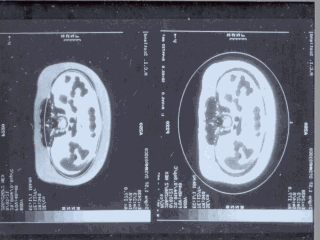

In the literature there is much attention on fat distribution

and its relationship to insulin resistance. These pictures show the peritoneal fat grains

directly into the portal circulation and metabolically much more active than subcutaneous

adipose tissue. So, the constant exposure of the liver to free fatty acids being released

in large amounts from this fat may explain the insulin resistance and hyperinsulinaemia of

the centrally obese subjects. |